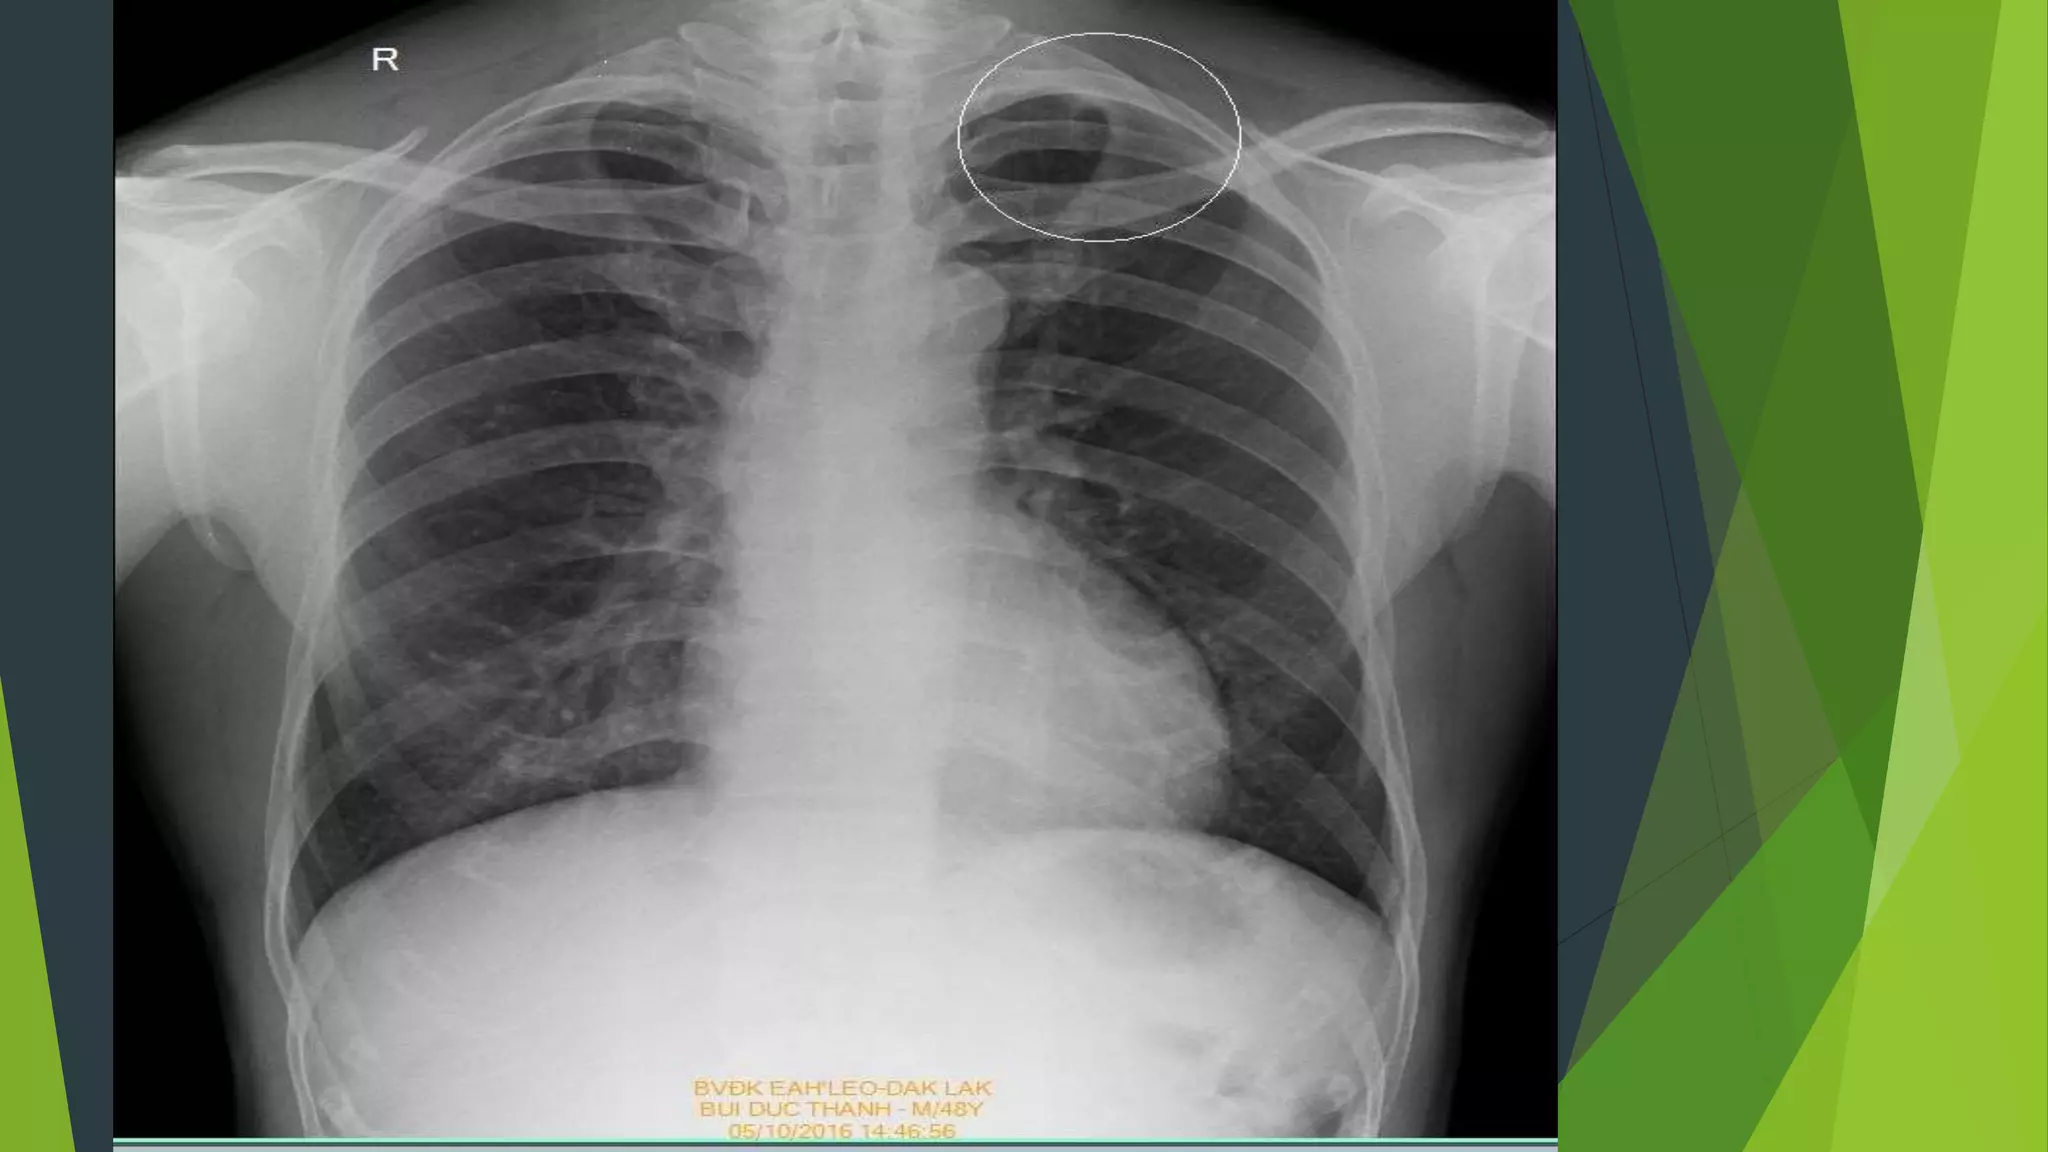

Lâm sàng: BN hơi tức ngực phải

Lâm sàng: BNhơi tức ngực phải